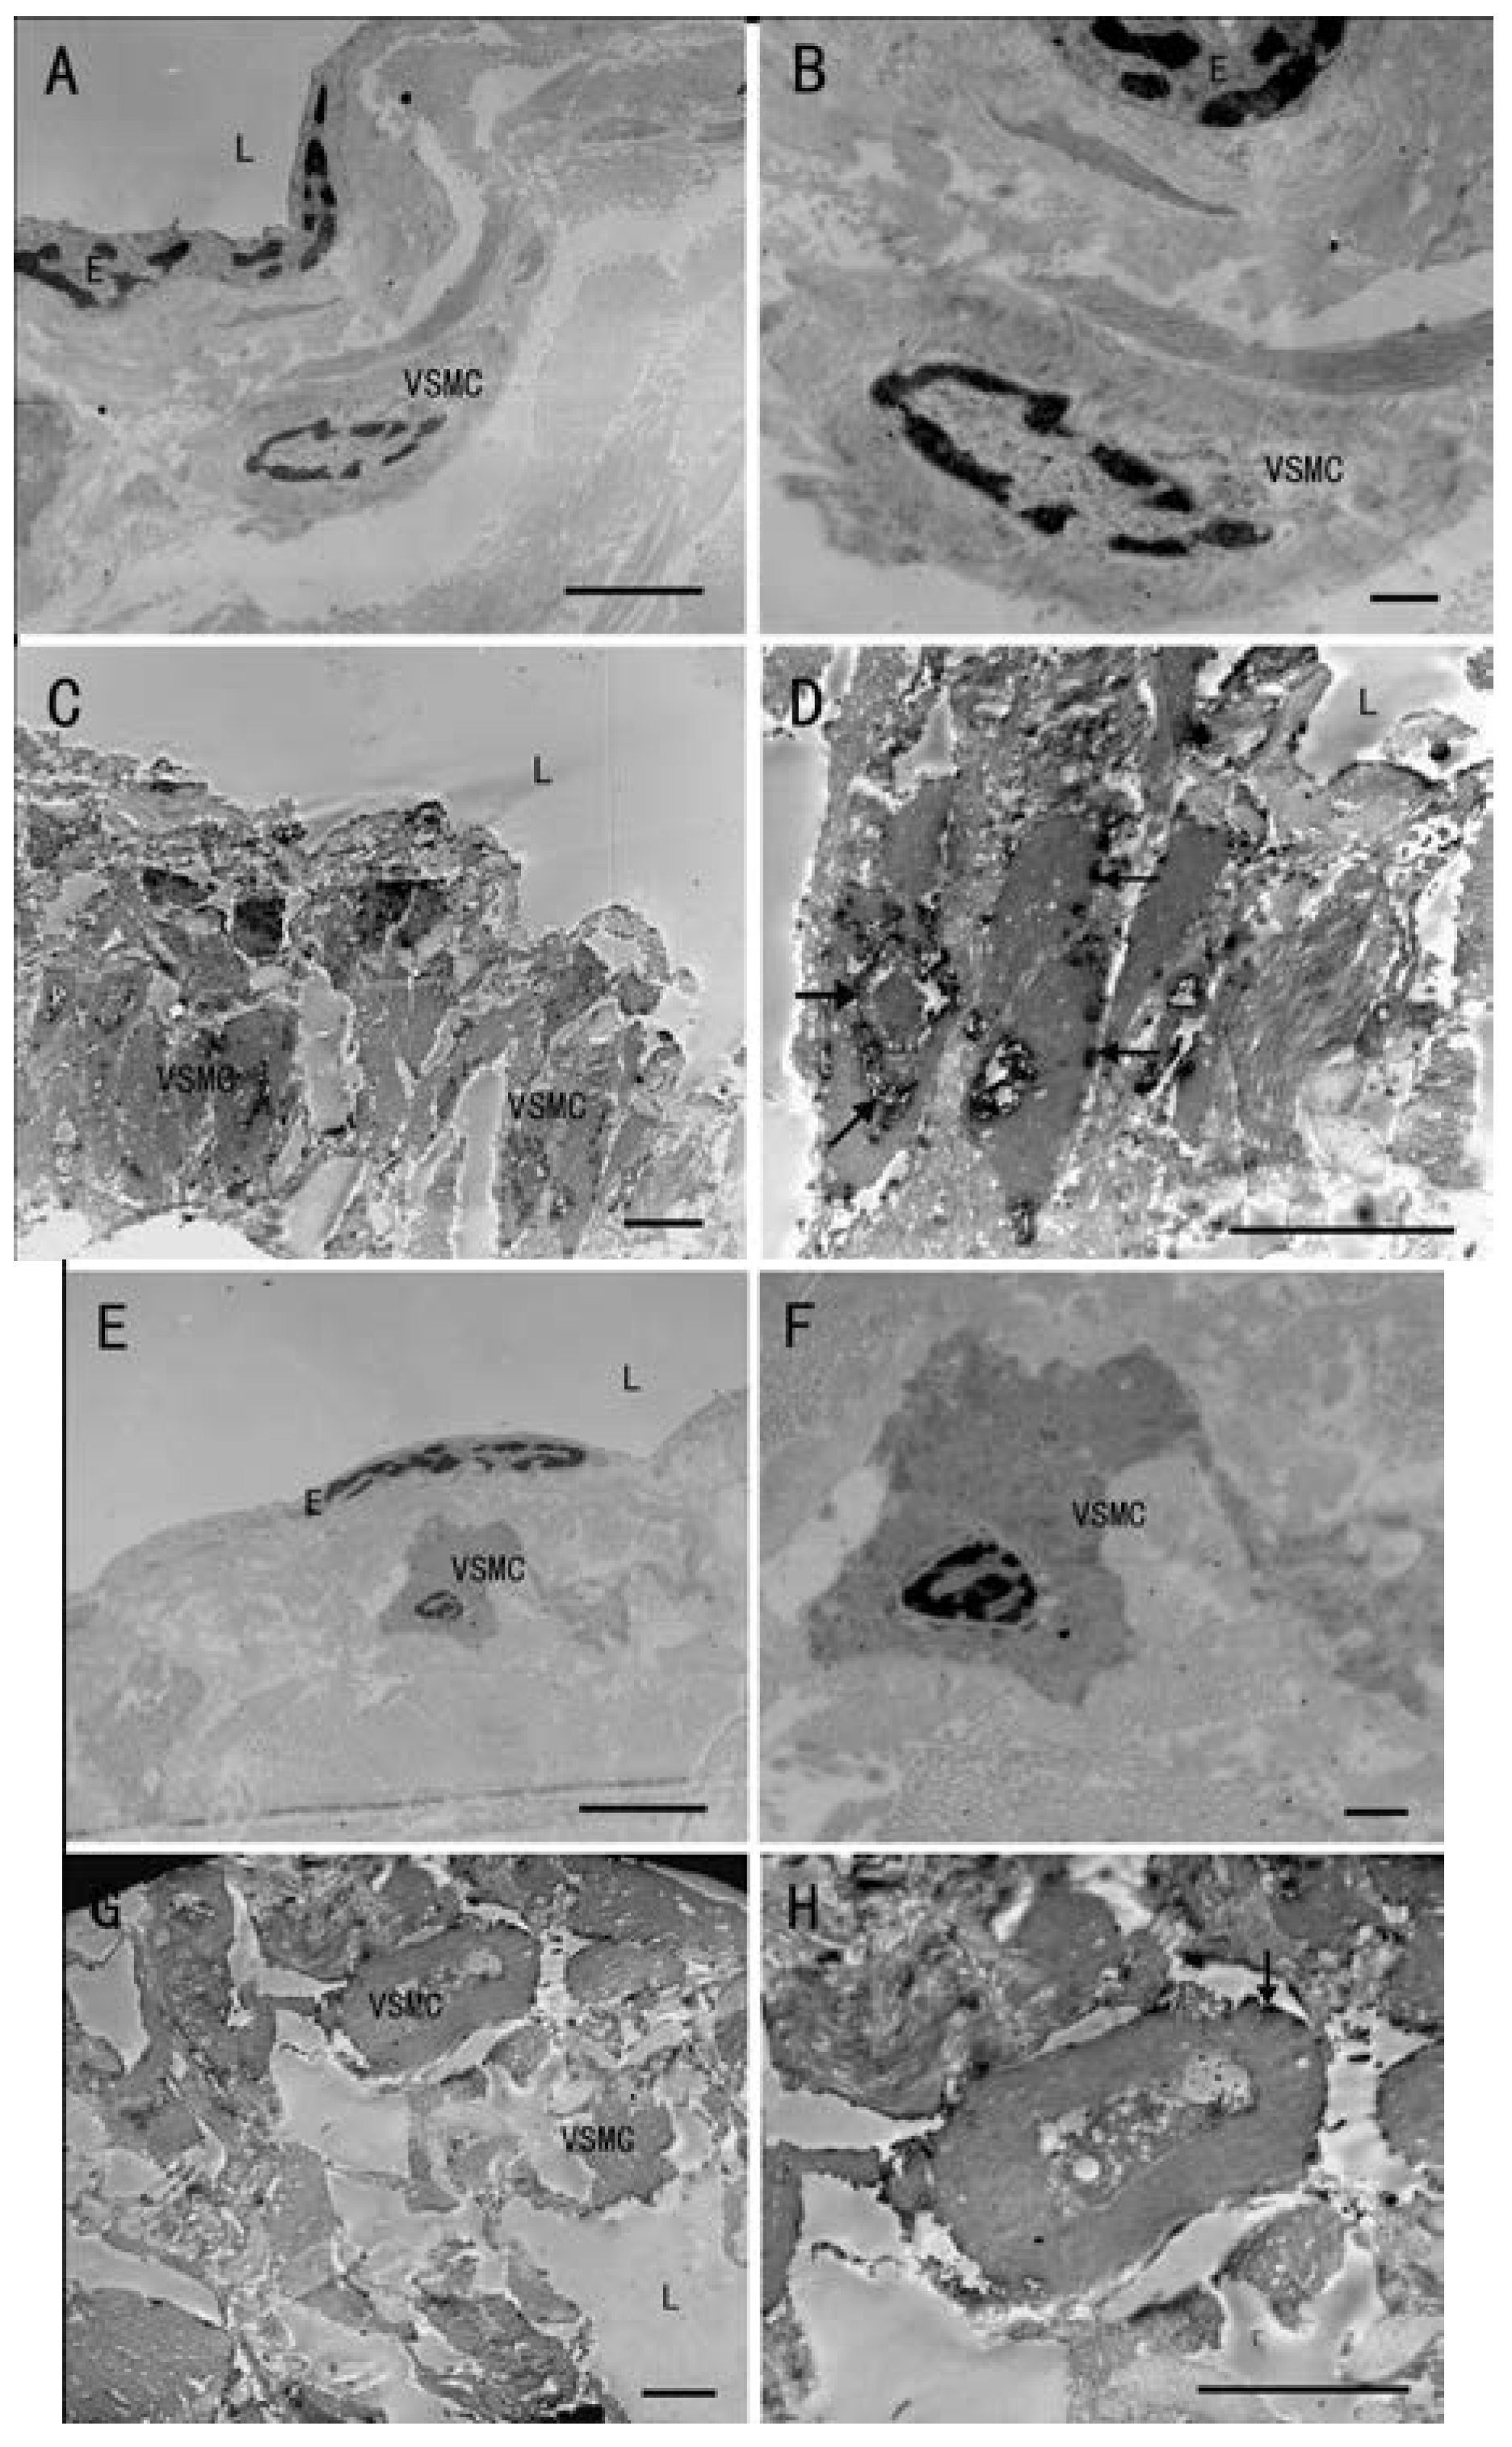

2.1. Observations of the Vein Wall by Hematoxylin and Eosin (H&E) Staining and Ultrastructure Change of Vascular Smooth Muscle Cells (VSMCs) by Transmission Electron Microscope (TEM)